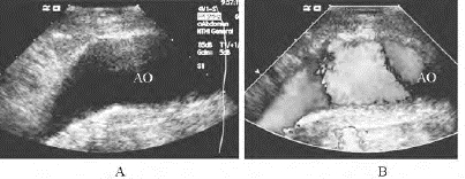

1.36.4四、腹腔大血管